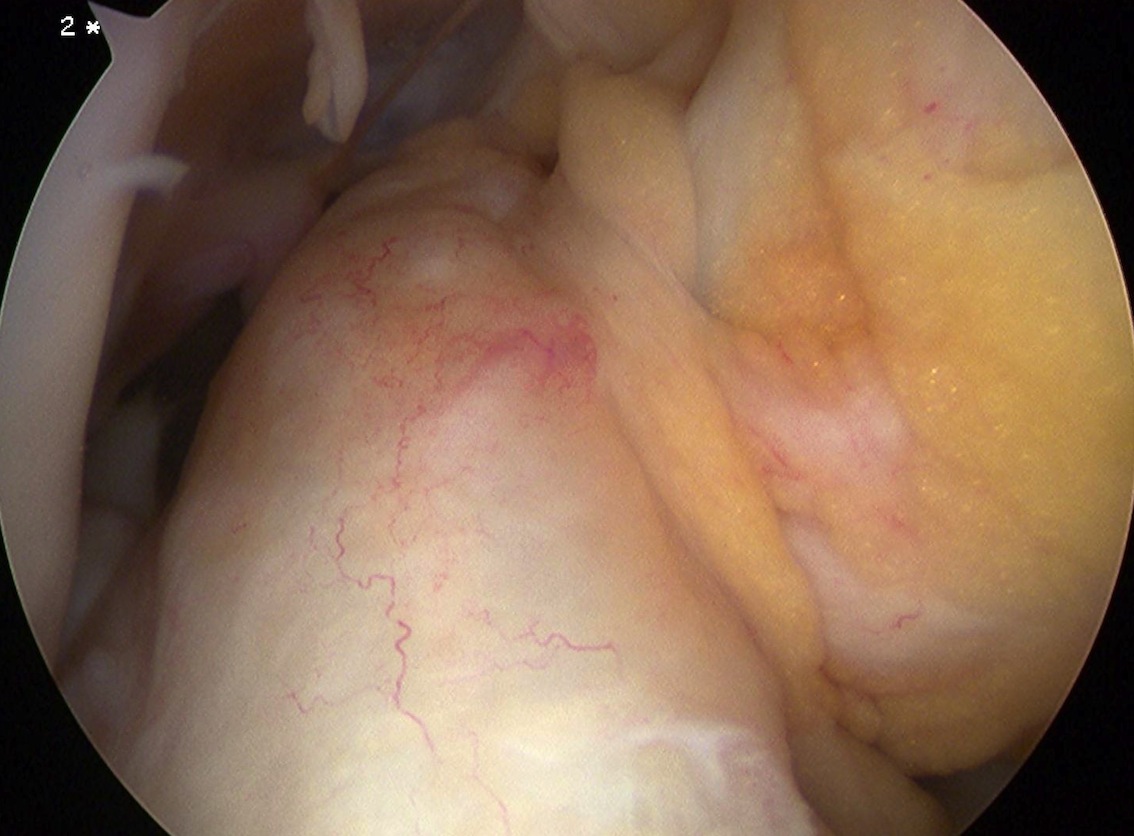

Arthroscopy images of right knee demonstrating normal ACL

Arthroscopy

Findings

- empty lateral wall

- ACL healed onto PCL

Arthroscopy of left knee showing no ACL attachment to lateral femoral condyle

Arthroscopy of right knee showing no ACL attachment to lateral femoral condyle

Arthroscopy of left knee demonstrating only a few minor fibres attached to lateral femoral condyle